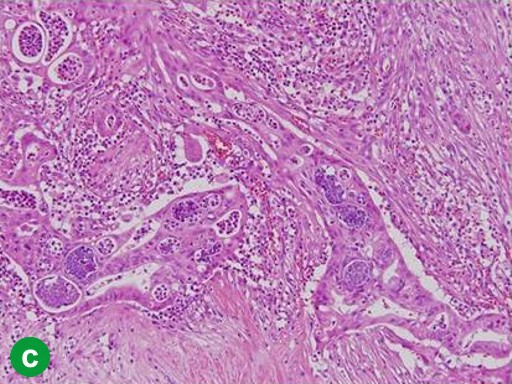

A 67-year-old man showed a pancreatic tumor on abdominal US at an annual medical checkup. An abdominal CT scan detected a 1 cm tumor in the body of the pancreas and main pancreatic duct dilatation of the distal pancreas (Figure 3a). A distal pancreatectomy with splenectomy was performed in February 2006. Histopathological examination confirmed a well-differentiated adenocarcinoma with no vessel or lymph duct invasion and no lymph node metastasis (Figure 3b). Mild atypical epithelia were observed at the cut edge of the main pancreatic duct (T1N0M0; R0; pathological stage: IA) (Figure 3c). Periodic checkups without adjuvant chemotherapy were carried out for 2 years, and there were no abnormal findings in abdominal CT scans or tumor marker assays.

Figure 3. Case#2: initial operation. a. A tumor approximately 1 cm in diameter and main pancreatic duct dilatation of the distal pancreas was detected in the pancreatic body on abdominal CT. b. Adenocarcinoma of the pancreas. Atypical cells with a swollen nucleus formed a papillary projection. c. Mild atypical epithelia projected from the cut edge of the main pancreatic duct. (H&E stain, x100). |